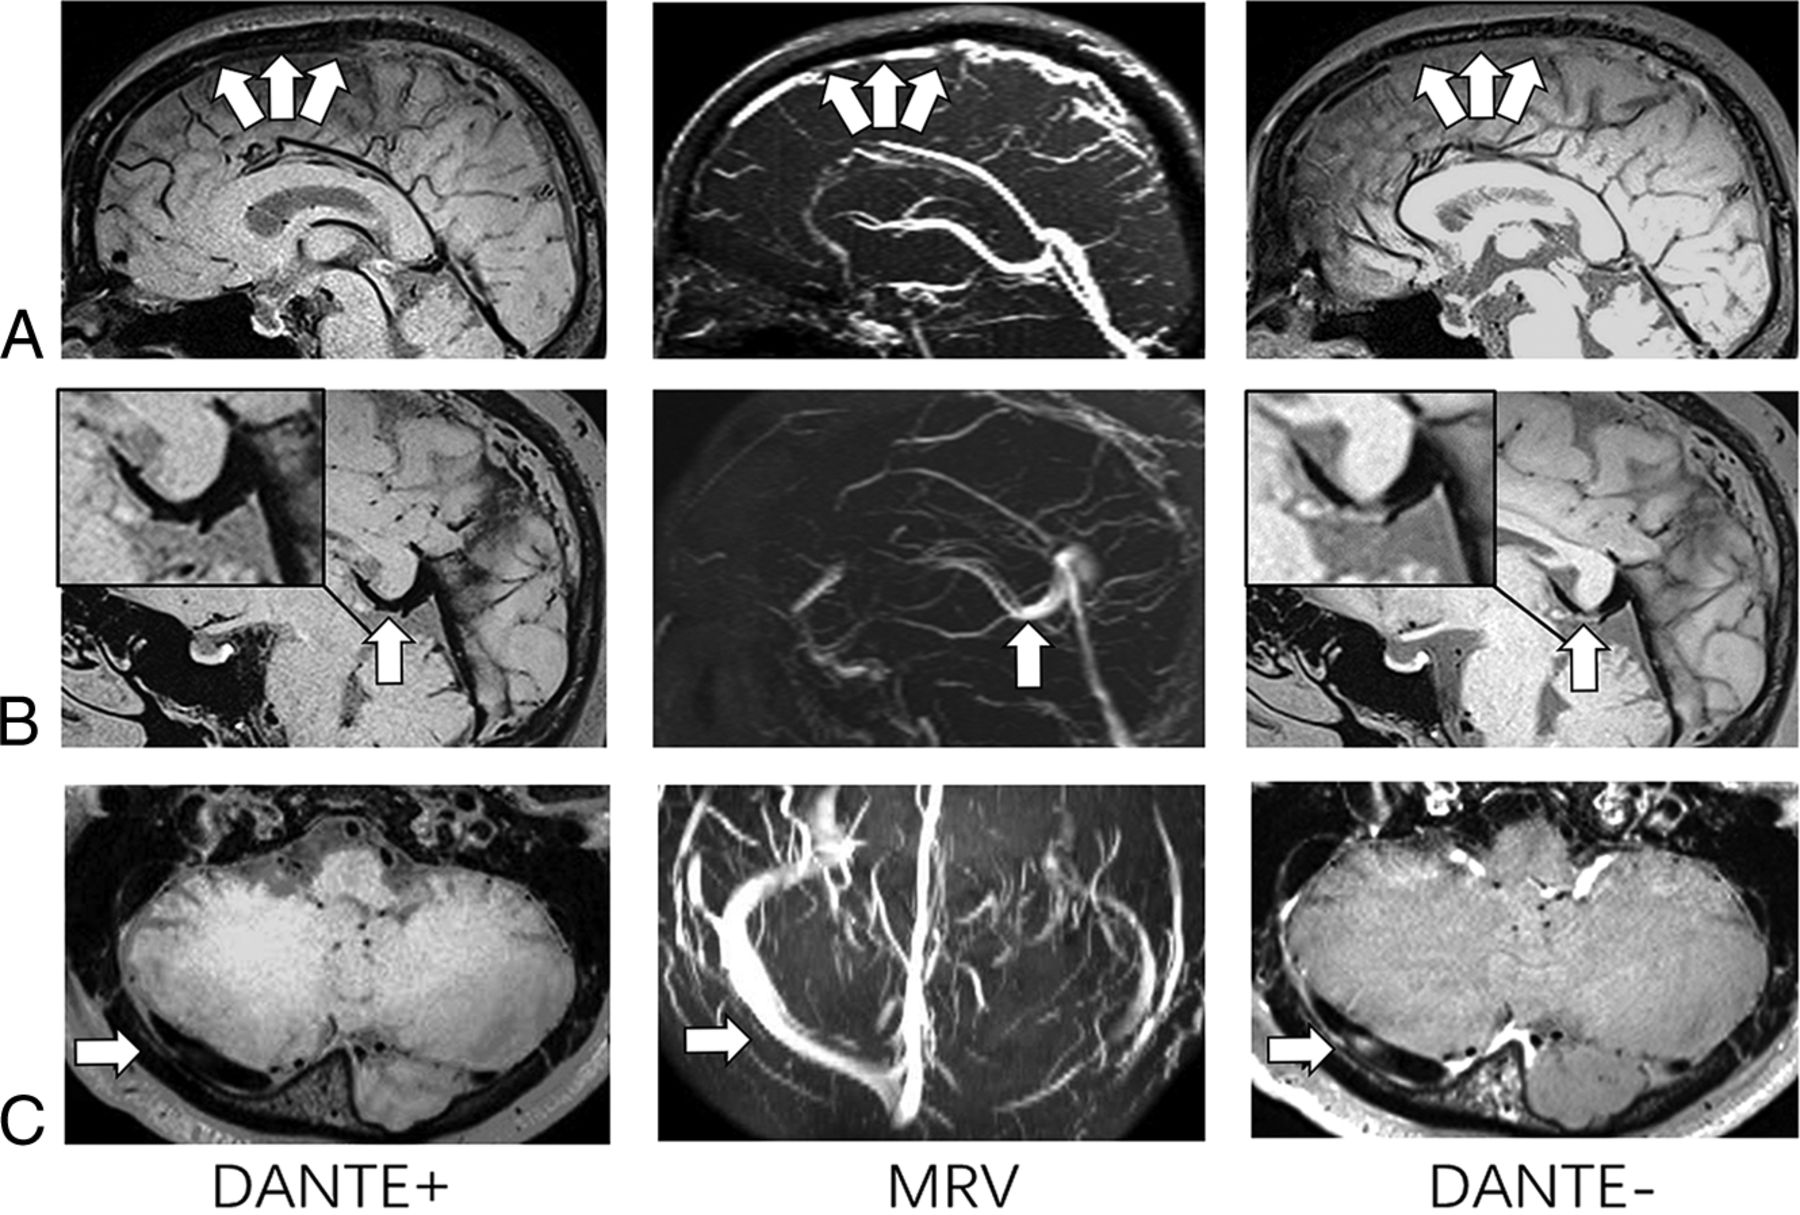

BTI (with/without DANTE preparation) images and MRV images of 3 patients with CVT. On BTI DANTE− images, isointense signals appear in the superior sagittal sinus (arrows, A), vein of Galen (arrow, B), and right transvers sinus (arrow, C). However, they are not shown on the BTI DANTE+ images (arrows). MRVs for these 3 patients demonstrate no filling defects on corresponding segments (arrows).

The clinical characteristics of patients are listed in Table 1. Two patients were clinically diagnosed with acute CVT (0–7 days after symptom onset); 2 patients, with subacute CVT (7–14 days); and 9 patients, with chronic CVT (≥15 days). CVT was detected in 11 subjects and 72 segments on conventional images. Blinded review of BTI reported apparent thrombi in 11 subjects and 77 segments on BTI DANTE+ but in 13 subjects and 94 segments on BTI DANTE− (Table 2). The agreement at the per-segment level between BTI and conventional imaging techniques was excellent for BTI DANTE+ (κ = 0.964) but moderate for BTI DANTE− (κ = 0.770). The specificities of CVT detection at the per-segment level were 96.3% and 83.8%, respectively, for the 2 different BTI techniques (Table 3). Representative cases are shown in Fig 2. In the 9 patients who were diagnosed with apparent thrombi in the superior sagittal sinus, the thrombus volume was significantly lower (4.814 ± 2.278 mL versus 6.341 ± 2.302 mL, P = .008) when using the DANTE preparation (Fig 3).